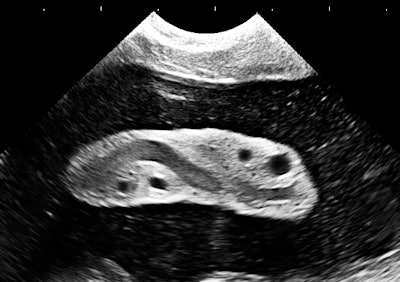

A common reaction to this image would be that there's nothing impressive about it, let alone that it might be worthy of featuring. Boring, next case, is it break time yet? The image above is an original, direct from the machine, with cropping but no additional postscan processing. It's about 5 years old, and its main technical flaw is lateral resolution spreading, which was really typical of beamformers and smaller-aperture arrays at the time. The markers atop the image are at 5-mm intervals.

There's not much noise in the image. There is flow streaming from platelet clumping and red cell rouleaux in the umbilical vein. The speckles in the amniotic fluid are real, being clumps of flaked-off skin and clear meconium.

This is actually a really good sign in second-trimester exams that you would miss in an image that incorrectly shows amniotic fluid as clear. Amniotic fluid is complex, like everything else in biology. An excellent review can be found in a 2005 article by Dr. Mark Underwood, Dr. William Gilbert, and Dr. Michael Sherman (Journal of Perinatology, May 2005, Vol. 25:4, pp. 341-348).

In medical imaging, picture aesthetics are always balanced by what you know about the target, like the normal and expected presence of meconium in the second trimester as a sign of well-being. This is the difference between the casual image viewer and the interpreter.

The central feature is a portion of the umbilical cord. It doesn't even seem to be a "good picture of the cord," which is most often depicted in 2D images as a simple cross section showing the big vessels. What it does show very well is a good amount of Wharton's jelly. Does that really have any meaning?